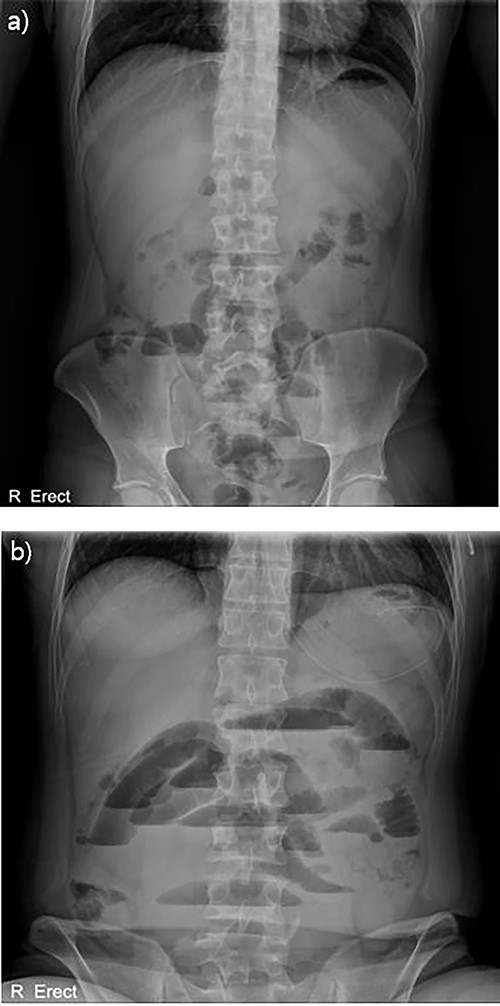

With no indications for immediate surgical intervention, the initial treatment plan for the patient was decided for conservative management with non per os (NPO) and Levin tube drainage. The patient, however, complained of aggravated abdominal pain after 12 h of conservative care, with elevated WBC count of 15 590/mm3. Changes were found in the abdominal X-ray showing manifestations of newly appeared step-ladder sign (Fig. 1a and b), and the CT scan displayed aggravated dilation of small bowel with a leading point of the mechanical obstruction in the LLQ area (Fig. 2).

Abdominal X-ray findings (a) initial findings before admission; (b) 12-h follow-up findings revealing step ladder sign.